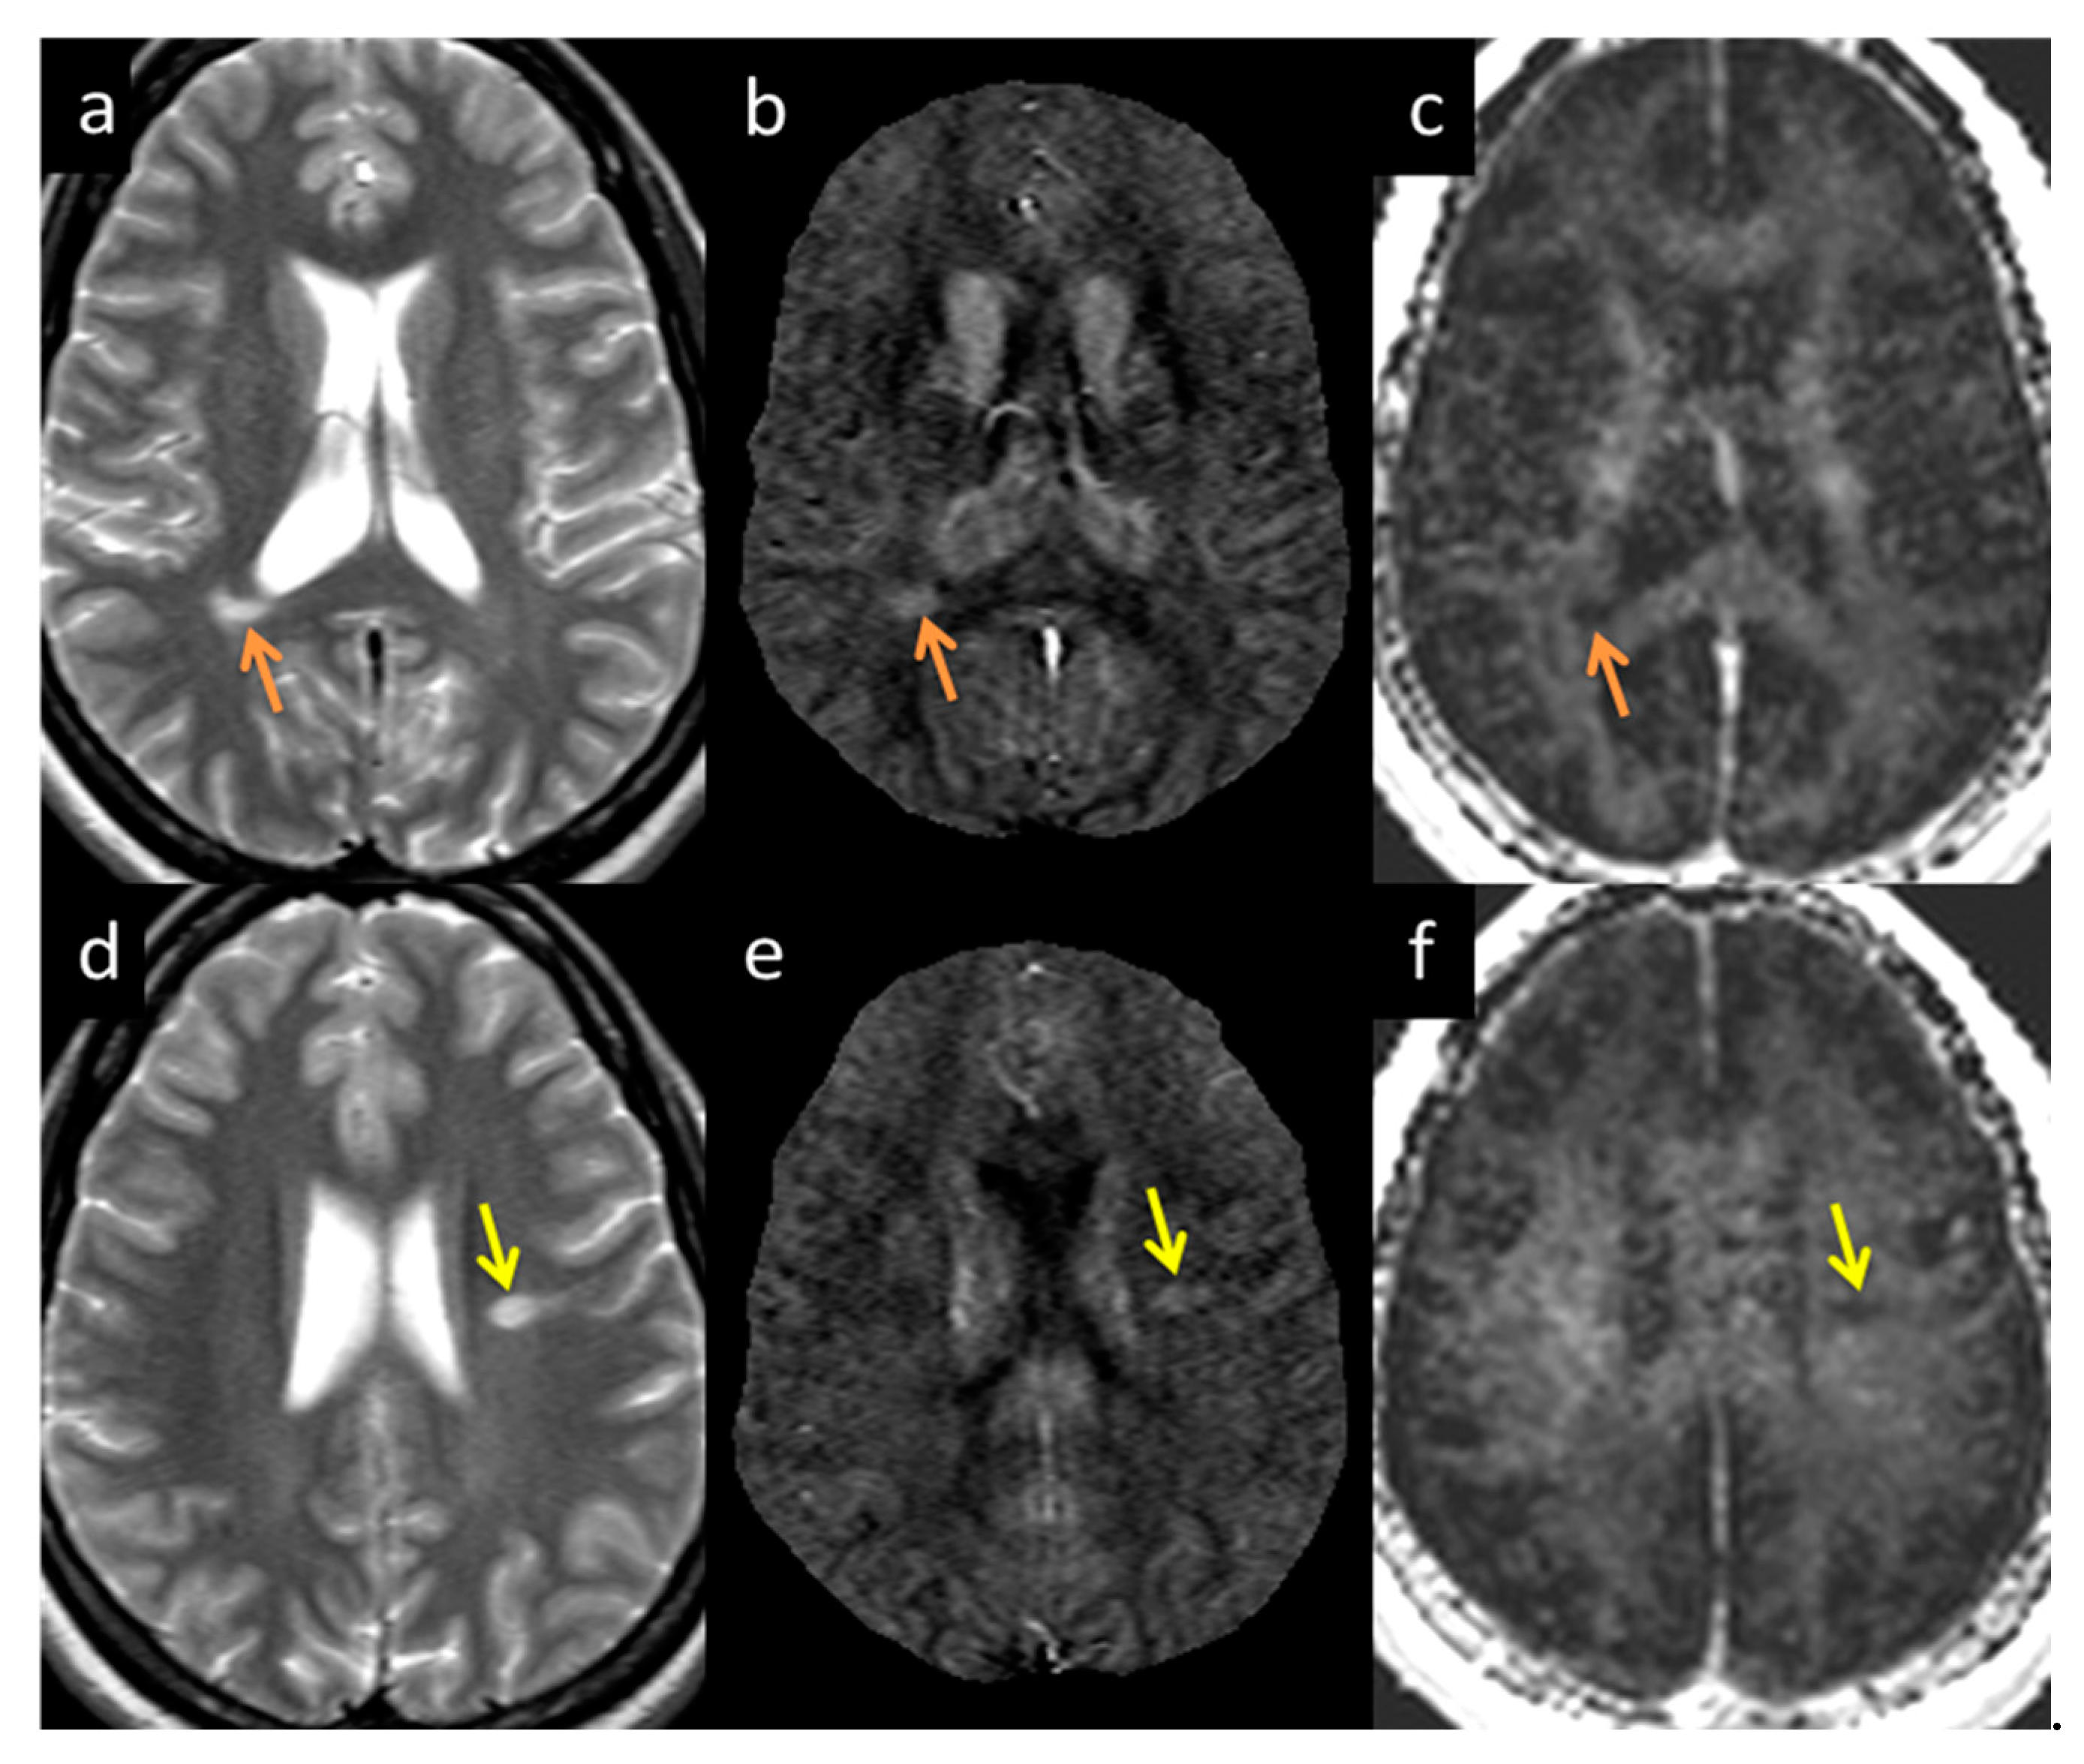

MWF had a thicker slice than other modalities and lower resolution, making it difficult to see smaller lesions; however, larger lesions could still be easily visualized. In total, 162 of 384 (42.2%) QSM-positive lesions and 29 of 94 (30.8%) QSM-negative lesions were visible in the MWF images. An example image showing MWF compared to other modalities is shown in Figure 7. The MWF correlated with susceptibility for QSM visible lesions, indicating that both methods were sensitive to loss of myelin fibers in white matter lesions (see Figure 8, p-value = 0.01). It can be seen from Figure 2 and Figure 7 that lesion appearance differs between modalities. FLAIR lesions are diffuse, lesions in modalities such as T1, T2WI, MTR are smaller and QSM lesions are local and have different volumes.

Figure 7.

Lesion appearance example in two different subjects: Subject 1 (a–c denoted by the orange arrow) and Subject 2 (d–f denoted by the yellow arrow) in T2WI (a,d), QSM (b,e), and MWF (c,f). The lesions appearing in MWF (c,f) also appear bright in QSM (b,e) with high susceptibility directly correlating to demyelination.